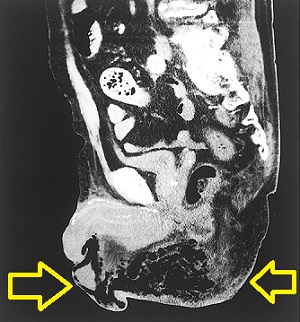

フルニエ壊疽(Fournier壊疽)とは外傷、尿路感染などから、陰部や肛門周囲へ急速に炎症が進行して起きるガス壊疽・壊死性筋膜炎です。

糖尿病やクリオグロブリン血症などの免疫低下・血流障害に

- 劇症型溶血性レンサ球菌感染症(A群β溶連菌)

- 嫌気性菌;陰嚢から会陰、肛門周囲にかけて握雪感

- クレブシェラ菌

などが感染しておこります。